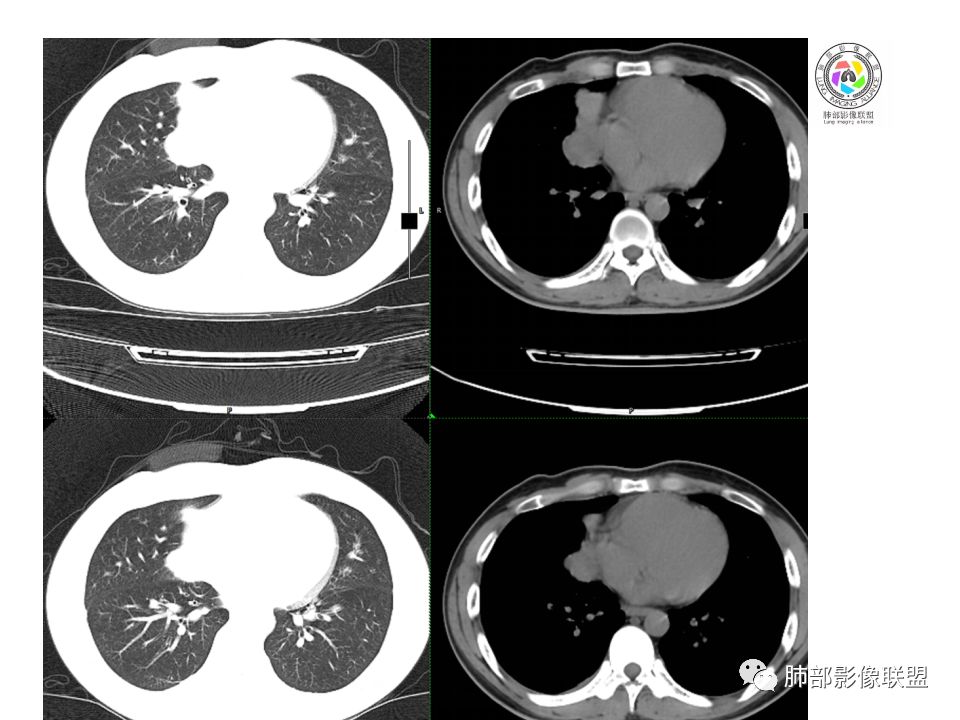

晨读:前纵隔占位,密度不均,沿着右侧纵膈延伸到肺门水平,周围支气管推移,大血管向内推移。临床有重症肌无力,考虑胸腺瘤可能,鉴别淋巴瘤。

右前纵膈肿块,偏一侧生长,形态欠规则,密度不均匀,其内可见小点状钙化,双肺多发小叶中心结节及钙化灶,右侧胸膜增厚(有陈旧性结核可能),青年男性(27岁),没有增强,考虑,1,前纵隔生殖细胞瘤2,精源细胞瘤

右前上纵隔占位,瘤肺交界面清楚,提示纵隔来源,其内有点状钙化,右侧胸腔积液,有临床症状,年龄轻,考虑生殖来源可能,胸腺瘤待排,请结合临床相关检查或CT增强进一步检查。

前纵隔占位,伴点状钙化;上腔静脉后移位。伴右胸膜局限性增厚,临床有重症肌无力,病人年轻,考虑胸腺瘤可能,鉴别生殖源性肿瘤。

右前纵隔占位,有分隔`低密度、点状钙化,边缘光滑,侵袭心包不明确,伴右胸少量积水,考虑恶性,生殖源性可能大,有视物不清,是否脑转移待查。建议HCG丶AFP检查。鉴别1:胸腺瘤、癌,30一40岁以下,少见,但有眼脸下垂,肌无力,待排除。2:淋巴瘤:侵袭性不强,有点状钙化,不支持。3:畸胎瘤:有低密度丶钙化,建议增强进一步明确。4:神经源性:一般后纵隔常见,不支持。5:LCD:症状少见,可以有树枝状钙化,浆细胞型可以有低密度,增强进一步明确

没有增强,好像两个病灶,上方三角形的像是胸腺增生。下方肿块,没有增强显得更难了,微钙化,轻度分叶,像有坏死低密度影,右侧少量胸水,胸膜受侵.,有视物模糊眼睑下垂。考虑胸腺瘤B1型及以上、B2型可能或生殖细胞瘤

前纵隔右区占位性病变,上区与胸腺延续,下区呈分叶状,尽管年龄<30还是首先考虑胸腺瘤,侵袭性可能性大(眼睑下垂不知是否有关)。鉴别主要是生殖细胞类肿瘤,主要是精原细胞瘤。另左肺上叶结核球,右侧胸腔积液,需除外结核性胸膜炎和转移

右前上纵膈肿块,内有点状钙化和少许小片状坏死,局部边界似欠清,右侧胸膜腔少量积液,年轻男性,小于30岁,有重症肌无力,虽然年龄偏轻,仍先考虑胸腺瘤,代排生殖源性肿瘤

晨读前纵隔肿块,偏右侧,密度不均,见点状钙化灶及分隔状低密度影。胸腺瘤>生殖细胞瘤>淋巴瘤

前中纵隔(胸腺癌区)不规则肿块,密度不均,有坏死区、点状钙化,边缘不会整肿块偏向右侧,向心包流注感,右胸腔少量积水。患者27岁,重症肌无力表现。

1.最常见的前纵隔肿瘤

2.发病年龄:40岁以上。30岁以下罕见

3.1/3出现重症肌无力,对诊断有提示意义

1.位于前纵隔,心包旁,颈根部可见

2.常偏侧性生长,呈半球状

3.外缘光整或可见分叶

4.长径5-10cm,大于15cm罕见

5.大多数密度均匀,少数可出现小片状的低密度区

6.钙化0-20%,常为被膜或被膜下弧形钙化,实质内钙化见于A型以上

7.约30%CT增强后见低密度的线样纤维分隔;少数富血供